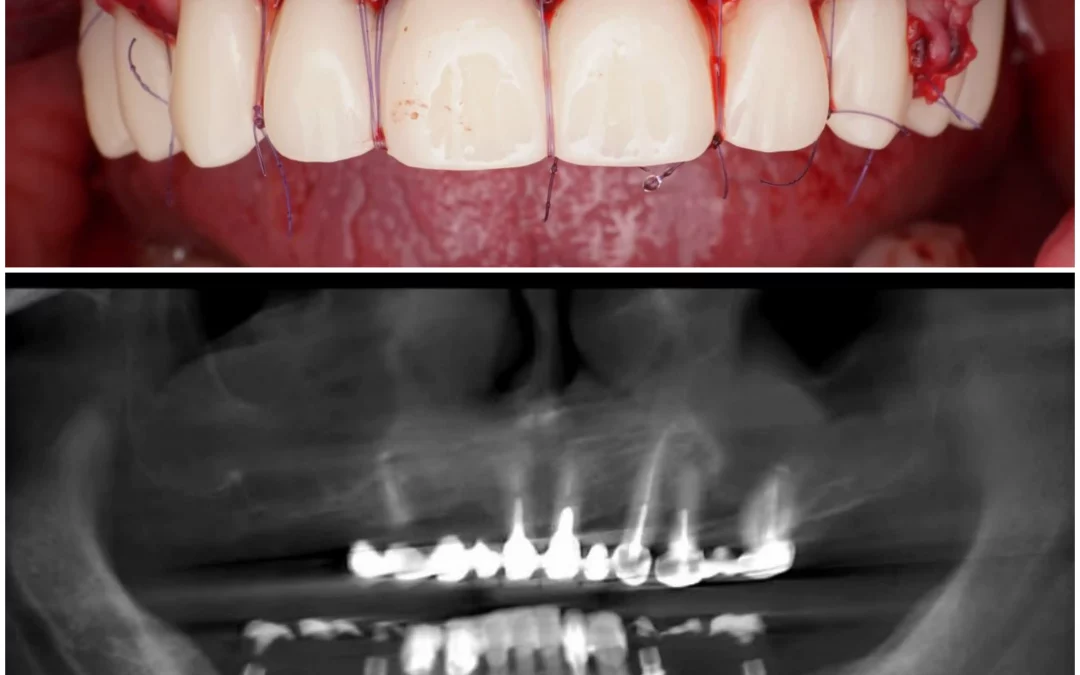

Юрий Гузеев | Клинический кейс YG-131

Восстановление объема и прикрепления. Работа с мягкими тканями в два этапа: 1 - Фиксация трансплантата к вестибулярному лоскуту. 2 - АСЛ. - Имплантаты MIS C1. - Connect. - Multi...